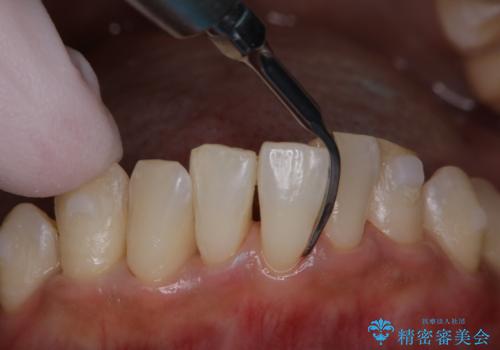

マウスピース矯正インビザライン治療では、歯の表面にアタッチメントという突起を設定します。(アタッチメントは歯の動きを効率的に移動するためのものです)

アタッチメントが歯に付くと、表面が凸凹し磨き残しが多くなったりと、プラークや歯石・着色がつきやすくなることがあります。

矯正治療中もPMTCを定期的に行い、専門的な機械でしっかりと汚れを除去することがおススメです。